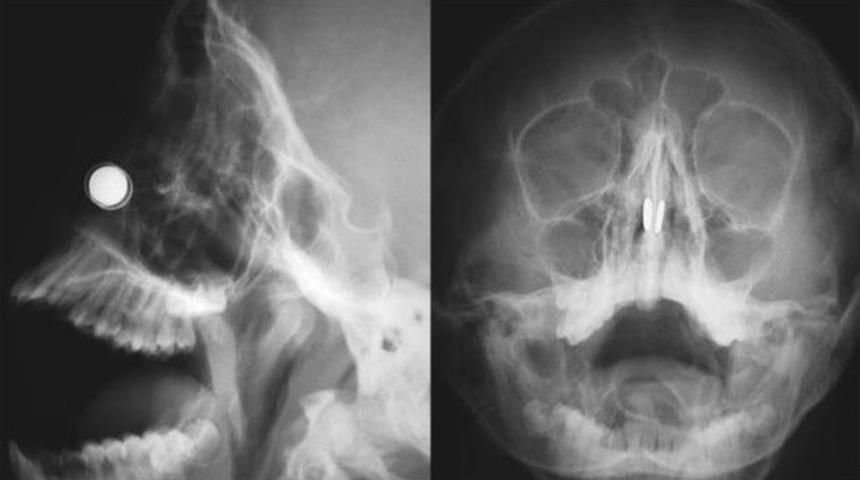

Bir süre önce her iki burun deliğine saat piline benzeyen küçük iki manyetik disk sokan 11 yaşındaki erkek çocuğunun, burnuna sıkışan mıknatısları çıkarmak için Doç. Dr. Kadir Çağdaş Kazıkdaş başkanlığında gerçekleştirilen operasyon Literatüre geçti.Konuyla ilgili açıklamalarda bulunan Yakın Doğu Üniversitesi Hastanesi’nde Doç. Dr. Kadir Çağdaş Kazıkdaş, en güçlü mıknatıslardan olan neodyum mıknatıslarının buruna girer girmez çocuğun burun direği etrafında birbirine yapıştığını açıkladı. Çocuğun mıknatısları burnuna soktuktan yaklaşık altı saat sonra dayanılmaz bir ağrı, burun kanaması ve burun içinde kabuklanma şikayetleri ile hastanenin acil servisine getirildiğini ifade eden Doç. Dr. Kazıkdaş, yapılan ilk müdahalede mıknatısların halen çocuğun burnunda olup olmadığının kesin olarak anlaşılamadığını, burun içerisinde de kanamaya bağlı çok fazla kabuklanma olduğunu, bu arada çocuğun duyduğu ağrı ve korku nedeniyle doktorların müdahale girişimlerini de engellediğini söyledi. Doç. Dr. Kazıkdaş daha sonra hastanın Kulak, Burun Boğaz Polikliniği’ne sevk edilerek, yüz röntgeninin çekildiğini, böylece burun içerisinde birbirine kenetlenmiş olan mıknatısların tespit edilebildiğini söyledi.Doç. Dr. Kazıkdaş; “Geleneksel Cerrahi Aletler ile Çıkarmayı Denedim Ama İmkansızdı!”Hızlıca ameliyathaneye alınan çocuğa genel anestezi verilerek bu esnada mıknatısları çıkarmanın bir yolunun arandığını söyleyen Doç. Dr. Kadir Çağdaş Kazıkdaş; “Çocuk septal perforasyon dediğimiz, burun direğinde küçük bir delik oluşması riski altındaydı. Aynı zamanda, eğer en kısa zamanda mıknatıslar çıkarılmazsa, burun kıkırdağında kangren ya da doku ölümü gerçekleşme olasılığı da vardı” dedi.Geleneksel cerrahi aletlerle mıknatısları çıkarmayı denediklerini ama bu şekilde sonuç alamadıklarını ifade eden Doç. Dr. Kadir Çağdaş Kazıkdaş, son olarak burun içinde kenetlenmiş olan mıknatısları kaldırıp çıkarmak için burun dışından sıradan mıknatıslar kullanmayı düşündüklerini ifade ederek şöyle devam etti; “Bu yöntem ile sol taraftaki mıknatısı kolaylıkla çıkarmayı başardık. Ardından ikinci mıknatısı çıkarmak da saniyeler sürdü. Çocuğun burun kıkırdağında oluşan hasarlı bölgeye ve travmatize olan dokulara yapay yama uygulandı. İlerleyen dönemdeki iyileşmeyi desteklemesi için silikon burun ateli de takıldı. Atel operasyon sonrasında on gün boyunca hastanın burnunda takılı kaldı.”Doç. Dr. Kadir Çağdaş Kazıkdaş, çocuğun altı ay sonraki takip muayenesinde, kalıcı hasar emaresi bulunmadığını ve rahatça burundan nefes alabildiğinin gözlemlendiğini belirtti. Doç. Dr. Kadir Çağdaş Kazıkdaş yaptığı açıklamada, mıknatıs kullanımının bir moda çılgınlığı olarak giderek popülerleşen bir olay haline geldiğini ve maalesef yetişkinlerde bile bu tür yabancı maddelerin kullanımı ile yaşanan olumsuz durumlarla daha sık karşılaşılmaya başlandığını söyleyerek, ailelerin mıknatıs ve düğme pilleri, çocukların ulaşamayacağı yerlerde saklamaları gerektiği konusunda uyarılarda bulundu. Bu tür objelerin küçük boyutta olmalarına rağmen şaşırtıcı derecede güçlü bir çekim kuvvetleri olduğunu ifade eden Doç. Dr. Kadir Çağdaş Kazıkdaş, takı ya da estetik amaçlar için kullanılabilecek olan mıknatısların potansiyel tehlikeleri ile ilgili daha büyük çocukların da bilgilendirilmesi gerektiğini söyledi.Çocuğun burnundaki mıknatısları çıkarma yöntemi, dış basında da yer bulduYakın Doğu Üniversitesi Hastanesi Kulak Burun Boğaz Anabilim Dalı ekibinin, 11 yaşındaki çocuğun burnundaki mıknatısları çıkarma yöntemi, dış basında da yer buldu.Kanada haber sitesi CTV News, konuyla ilgili haberi “Doktorlar, çocuğun burnunda sıkışıp kalmış mıknatısları çıkarmak için mükemmel bir yol buldular”, Amerikan radyo kanalı ve haber sitesi National Public Radio ise “Bir Çocuğun Burnuna Mıknatıs Sıkıştığında, Doktorlar Hassas Davranmak Zorundadır” başlığıyla duyurdu.The New England Journal of Medicine ise bu konu hakkında yayınladığı makalede, mıknatısların çok uzun süreden beridir çocuklar için bir sağlık sorunu oluşturduğunu, 2013 yılında Annals of Emergency Medicine’da yapılan çalışmada, 2001 ve 2002 yılları arasında, 21 yaş altı 22.500’den fazla kişide mıknatısla alakalı yaşanmış kaza tespit edildiği, mıknatısların vücuda ağır hasar verebileceği, hatta ölüme neden olabileceğinin göz ardı edilmemesi gerektiği ifade edilerek, Kıbrıs’ta yaşanan vakada doktorların sorunu dahiyane bir şekilde çözüme dönüştürmeyi başardıklarını yazdı.Norfolk’daki The King’s Daughters Hastanesi Pediatrik Kulak Burun Boğaz Bölümü yöneticisi Dr. Craig Derkay ise “Hemen hemen hergün çocukların kulaklarından, burunlarından ve boğazlarından bir şeyler çıkarıyoruz. Özellikle saatlerde ve oyuncaklarda bulunan düğme pillerden endişe duyuyoruz. Shots’un 2012 de belirttiği gibi bunlar yanmalara ve doku ölümüne yol açabilirler. Neyseki burnunda mıknatıs sıkışan çocuğun durumu güzel bir şekilde sona erdi.” dedi.